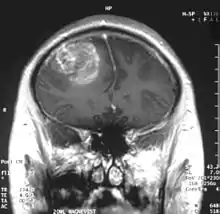

- L'imagerie par résonance magnétique est trop peu sensible pour représenter le passage de substances actives à travers une barrière hémato-encéphalique saine. En cas de lésion, l’IRM avec produit de contraste joue un grand rôle.

D'autres pathologies peuvent perturber le fonctionnement des endothéliums « du dedans vers le dehors », c'est-à-dire que des influences provenant de la matrice extracellulaire perturbent l'intégrité de la barrière hémato-encéphalique. Par exemple, on a le glioblastome[53].

Le premier produit de contraste mis au point pour l'IRM est le gadolinium (Gd). En raison de sa toxicité, il faut l’emballer (le chélater) dans une molécule de DTPA. On a ainsi obtenu en 1984 le Gd-DTPA[81], qui avait le potentiel pour obtenir des IRM renforcés pour le diagnostic de lésions locales de la barrière hémato-encéphalique[82]. La molécule de Gd-DTPA est très polaire, et par conséquent bien trop hydrophile pour traverser une barrière hémato-encéphalique saine. Les modifications des jonctions serrées, comme celles qui peuvent par exemple être provoquées par un glioblastome, permettent le transport paracellulaire de ce produit de contraste dans le tissu cérébral. Là, il renforce le contraste, par interaction avec les protons de l'eau environnante, et rend visibles les défauts de la barrière hémato-encéphalique. Comme ce sont les vaisseaux responsables de l'alimentation de la tumeur qui sont touchés, dans son voisinage immédiat, on peut en apprécier l'extension.